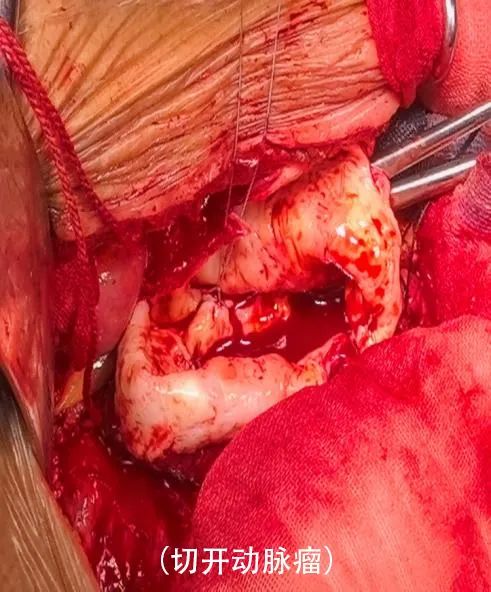

手术采取“腹主动脉瘤切除+人工血管置换术”的方式,通过全麻下开腹暴露腹主动脉瘤,阻断病变段主动脉血流后切除瘤体,用人工血管与正常血管断端吻合,重建血流通道。

●开放手术是传统的手术方式,医生会在腹部切开,直接修复或替换受损的动脉部分。这种手术虽然有效,但恢复时间较长,术后可能会有一些并发症。

(腹主动脉瘤开放手术)